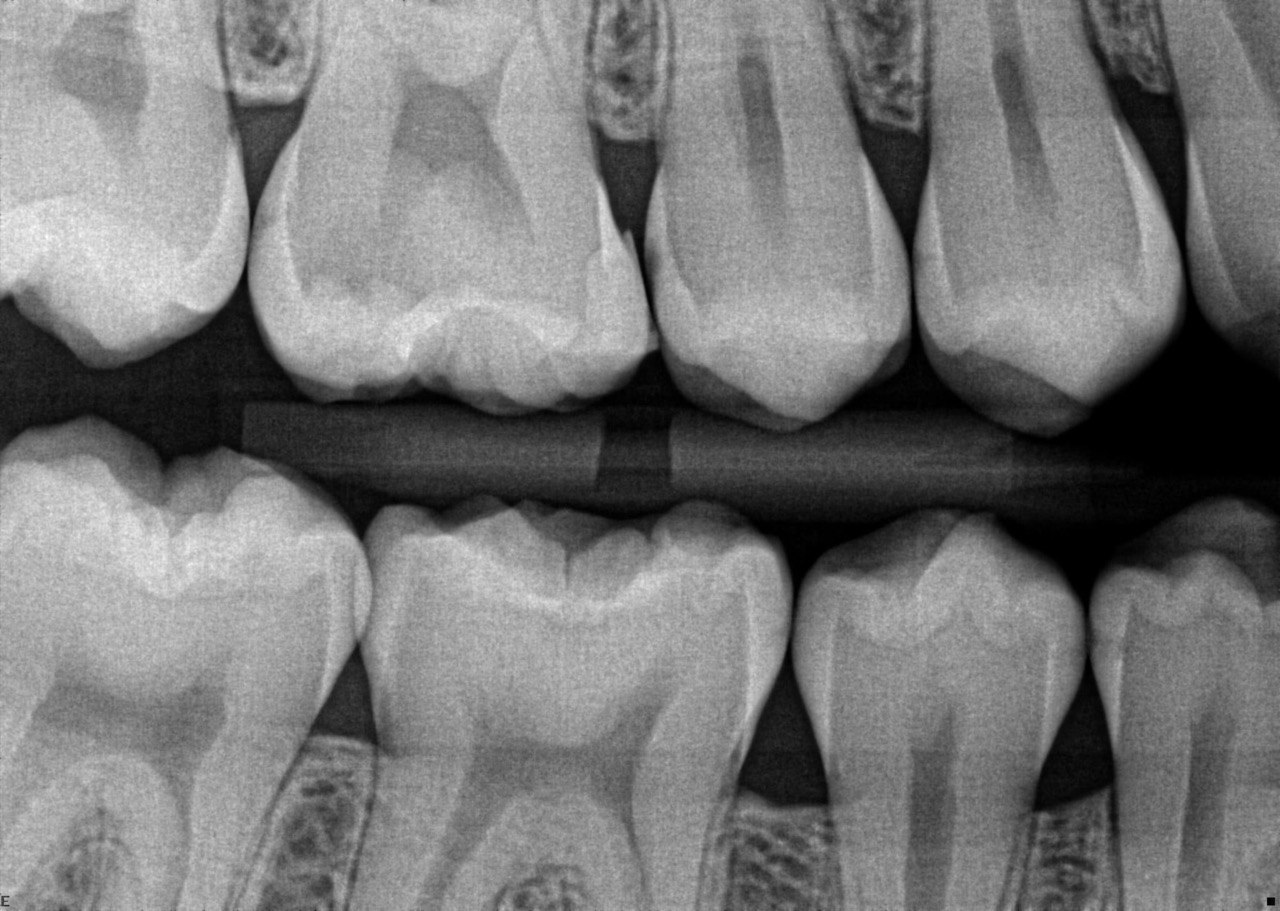

32. Which surfaces needs restoration?